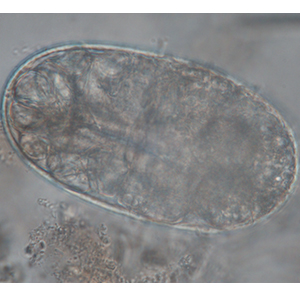

Les œufs de strongle présentent globalement la même morphologie ; ce sont des œufs ovalaires, à paroi lisse, possédant une morula et des faces latérales non parallèles. Leur taille est très variable (40 x 60 μm à 110 x 230 μm) et les groupes évoqués ci-dessus peuvent présenter des caractéristiques permettant d’orienter le diagnostic mais ces dernières sont à prendre avec précaution. Ces œufs, lorsqu’ils persistent longtemps dans le milieu extérieur, peuvent présenter un embryon vermiforme (Garcia, 2021).

- Les anguillules(Strongyloides): ces nématodes rentrent dans le diagnostic différentiel des œufs de strongle embryonnés. A l’inverse des œufs de strongles, ils mesurent 40-70 μm de longueur pour 20-35 μm de largeur, possèdent une paroi très fine et leurs faces latérales sont parallèles (Garcia, 2021).

- Les acariens: les œufs d’acarien sont plus gros que la plupart des œufs de strongles (100-140 μm de longueur pour 50-80 μm), ils présentent également un contenu granuleux, avec de nombreuses vacuoles nutritives. Lorsque l’embryon est développé, il prend une forme caractéristique d’acarien (Petithory et al., 1995).

- Les trachéides: certaines cellules végétales peuvent prendre des dimensions proches de celles des œufs de strongle. Elles peuvent être remplies de matériel granuleux et mimer la forme de ces derniers. La paroi est néanmoins plus épaisse et la forme plus anguleuse (Petithory et al., 1995).